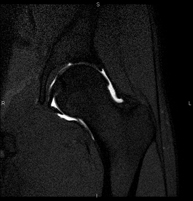

Artro-RM de Maluc

Artro-RM de MalucExploració per estudiar les lesions en petites estructures anatòmiques de l'articulació que solen produir-se en pacients que pateixen luxació o pinçament (disminució de l'espai). L'estudi ve precedit per una injecció de contrast a l'interior de l'articulació, realitzada sota control de raigs X. La durada total dels dos procediments és de 50 minuts.